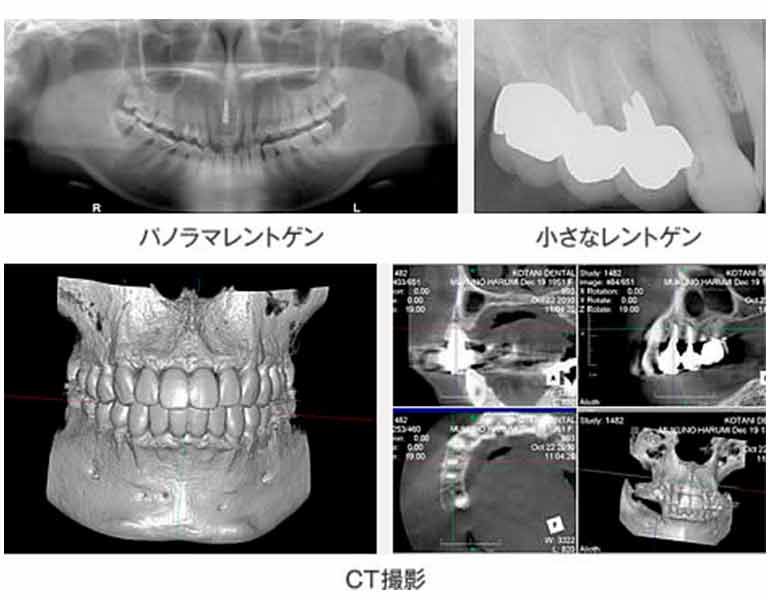

レントゲン・写真撮影

目では見えない部分をレントゲン写真を撮影することで診査していきます。 口腔内から顎の骨や関節までを大まかに一望できる パノラマレントゲン写真を一枚、細かな部分的な状態を観察するための小さなレントゲン写真を10枚撮影いたします。

通常レントゲンで分かりづらい箇所やインプラント治療をご希望の方はCT撮影を行います。